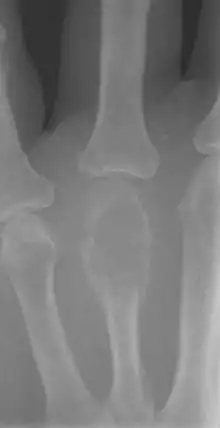

| Non-ossifying fibroma of tibia | |

The most common bone tumor is a non-ossifying fibroma.[4] Average five-year survival in the United States after being diagnosed with bone and joint cancer is 67%.[5] The earliest known bone tumor was an osteosarcoma in a foot bone discovered in South Africa, between 1.6 and 1.8 million years ago.[6]

Primary bone tumors

Primary tumors of bone can be divided into benign tumors and cancers. Common benign bone tumors may be neoplastic, developmental, traumatic, infectious, or inflammatory in etiology. Some benign tumors are not true neoplasms, but rather, represent hamartomas, namely the osteochondroma. The most common locations for many primary tumors, both benign and malignant include the distal femur and proximal tibia (around the knee joint). Examples of benign bone tumors include osteoma, osteoid osteoma, osteochondroma, osteoblastoma, enchondroma, giant cell tumor of bone and aneurysmal bone cyst.